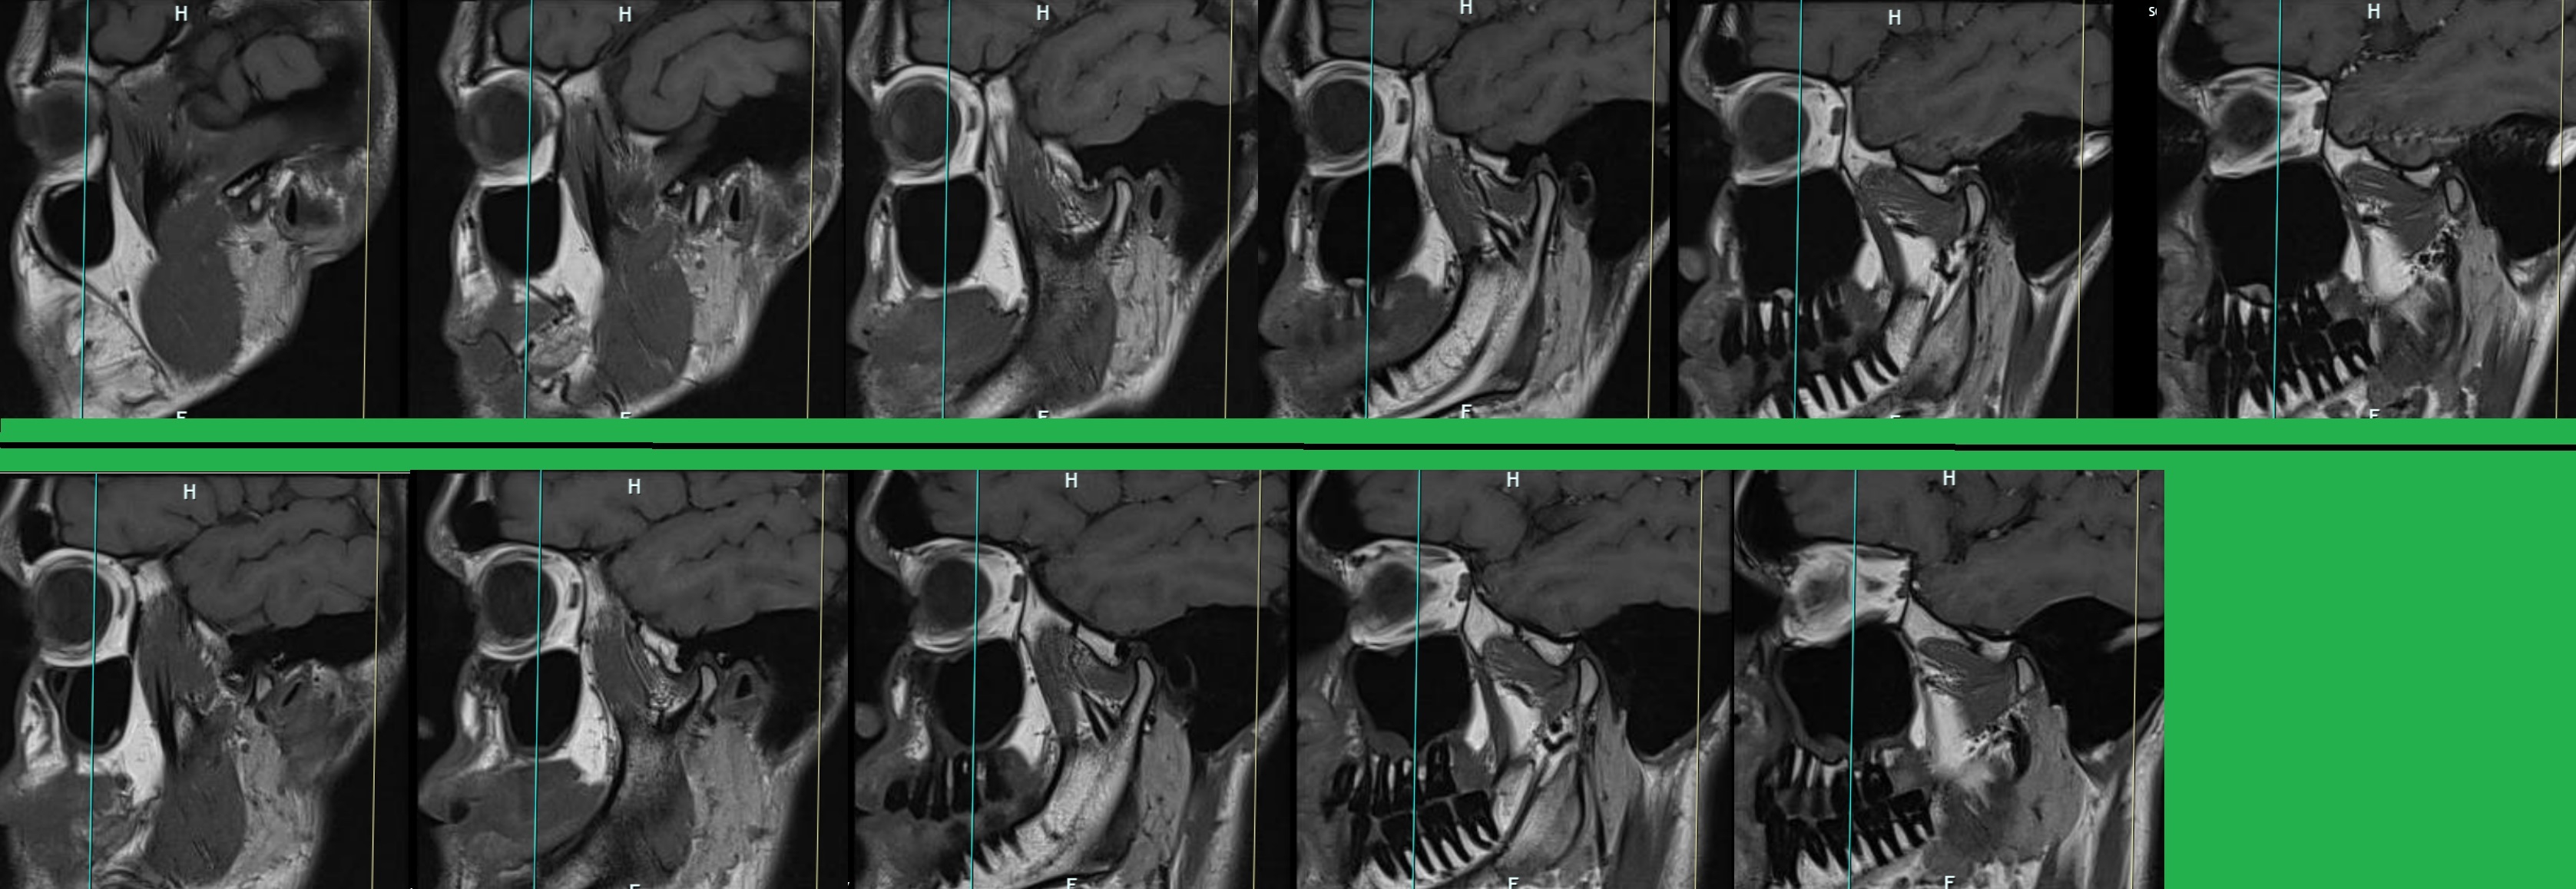

В опщем сходил вчера к ревматологу. Все анализы крови отличные, и CRP и Ana и Anti-CCP. Хламидии, иерисинии и борелии тоже не показывает, и рентгены рук ног тоже хорошие. Дал направление на МРТ рук, сказал пить 3 недели повышенную дозу преднизолона (первую неделю 10 мг, потом 7.5 потом 5). И следующее посещение в конце августа.

Я кстати так и не смог зарегаться на твоем форуме ревматиков.нет, >>1549389 письма на почту не приходят, разные пробовал, у многих людей такая же проблема...

Мне кажется дело может быть в Streptococcus Pyogenes но врач чет не захотел делать ASLO тест в крови, сказал что это устаревшее и ничего не показывает. Что думаете?

Ещё и откуда-то антитела на гепатит Б взялись, хотя я ваще не помню чтоб я прививался или болел им...